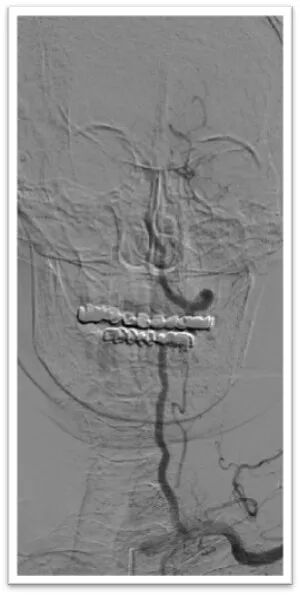

支架长鞘在远端保护下采取抽拉结合技术

Synchro2微导丝引导微导管通过闭塞段后造影位于血管真腔,交换长导丝Synchro 300mm,顺利置入保护伞Spider 4mm于岩骨段,微导管释放6-30mm支架后造影显示支架完全覆盖血栓,正向血流未完全恢复,停留5分钟后在支架锚定下前推长鞘,使用抽拉结合取栓术取出大量血栓;